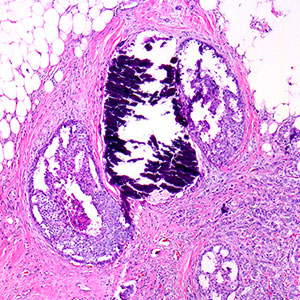

La soluzione di eritrosina B arancio viene utilizzata per la colorazione del citoplasma e connettivo nella colorazione di biopsie osteomidollari secondo la metodica di Dominici.